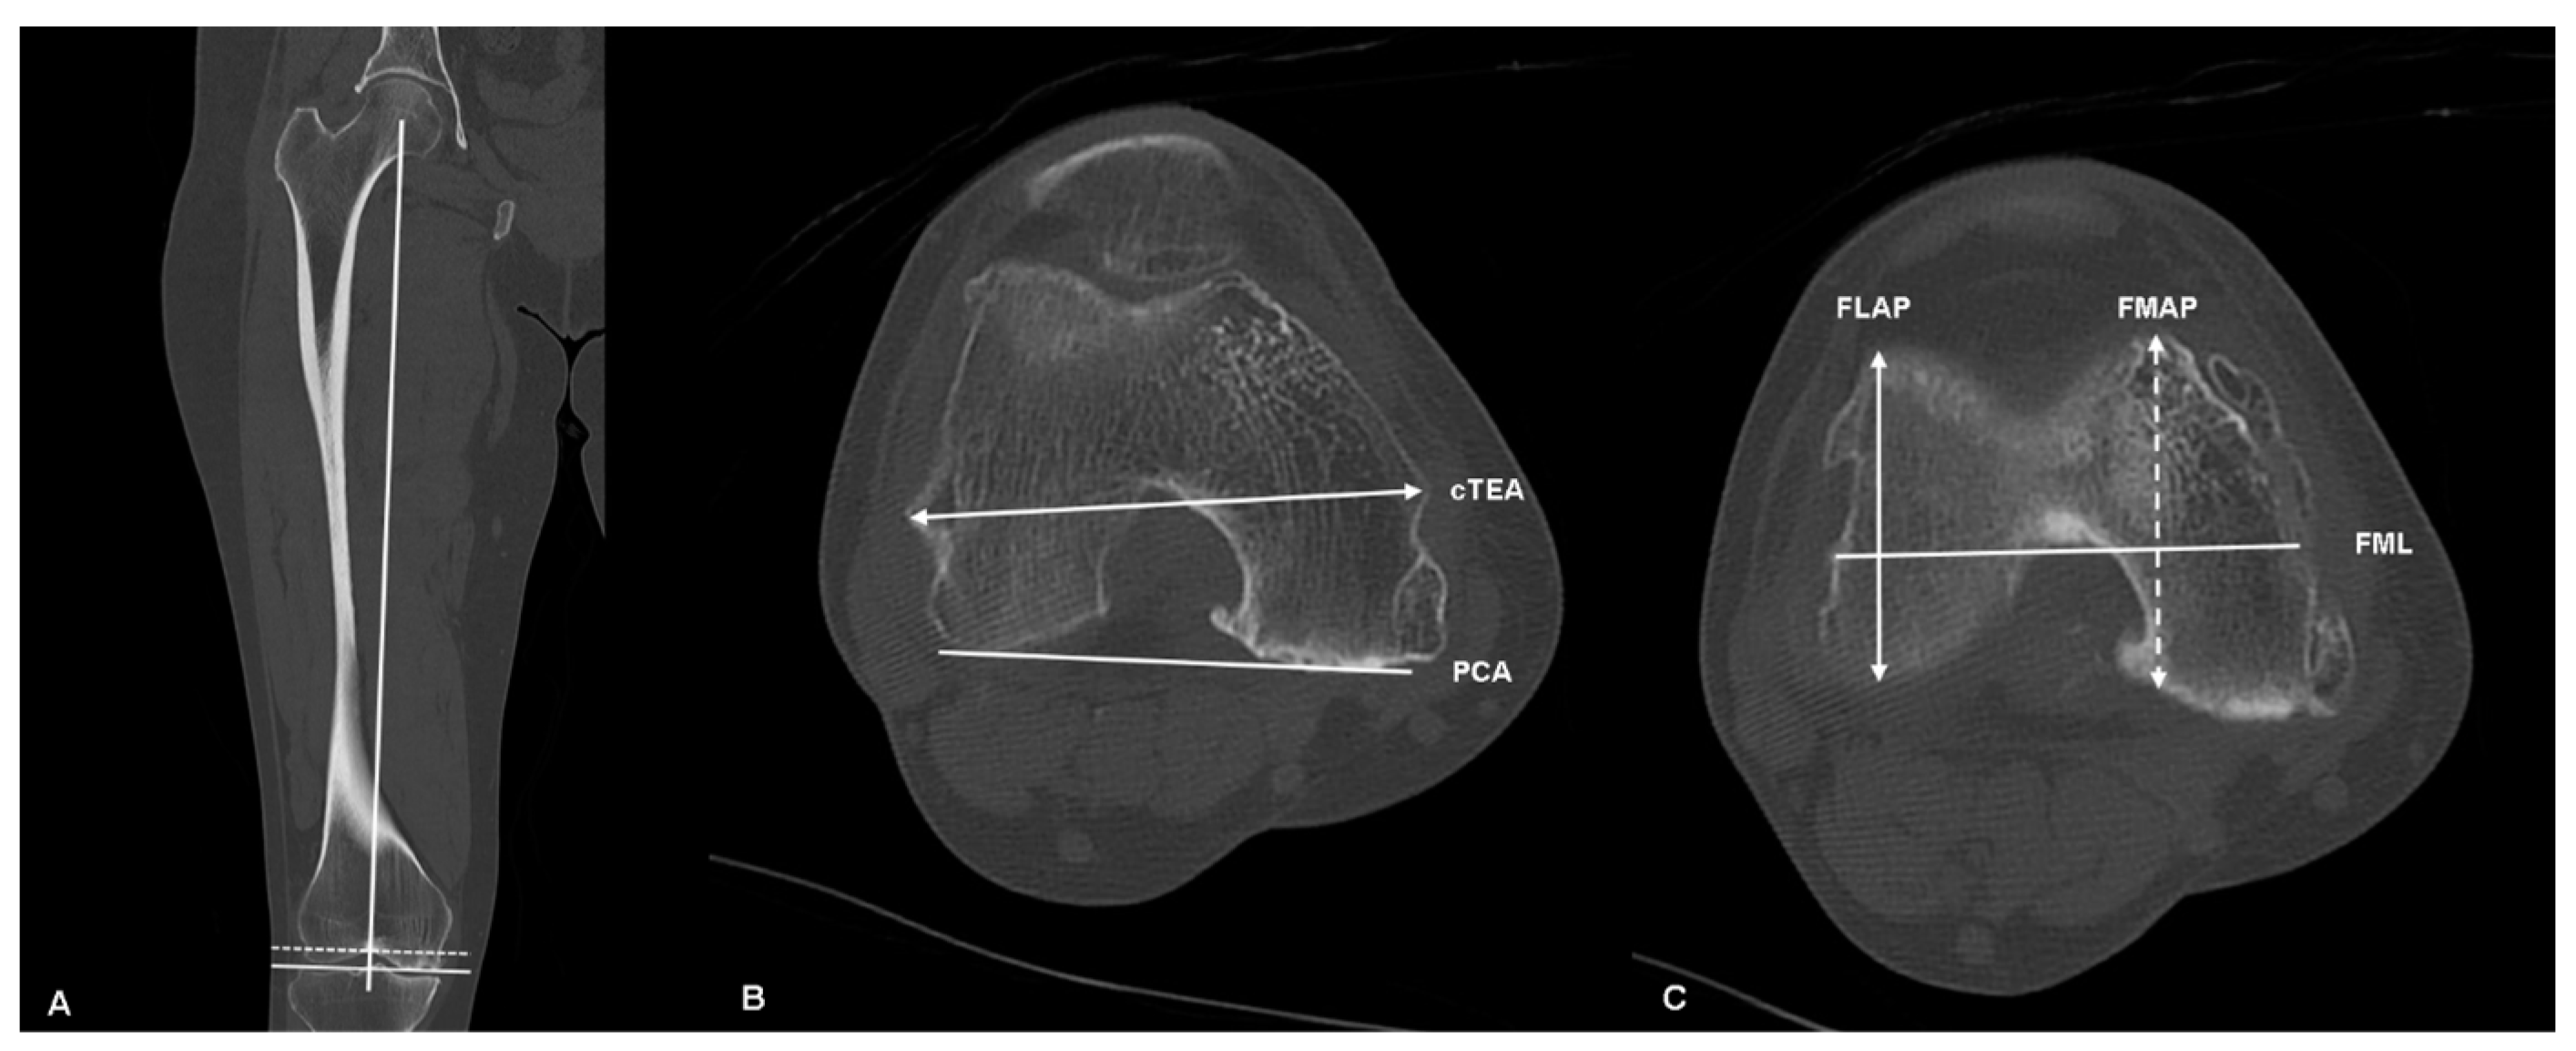

| cTEA-PCA | 5.4° ± 2.1 |

| FLAP | 52.4 mm ± 3.9 |

| FMAP | 55.2 mm ± 3.8 |

| dFAP | 2.8 mm ± 3.6 |

| FML | 68.2 mm ± 4.7 |